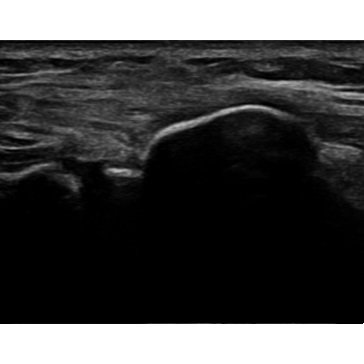

At the consultation, a platelet-rich plasma (PRP) injection was recommended due to persistent pain and instability. She underwent an ultrasound-guided PRP injection into the proximal tibiofibular joint (PTFJ) five months after the initial injury. At the time of the injection, point-of-care ultrasound revealed a hyperechoic lesion at the PTFJ Case Photo #8 , suspected to be scar tissue contributing to her ongoing pain.